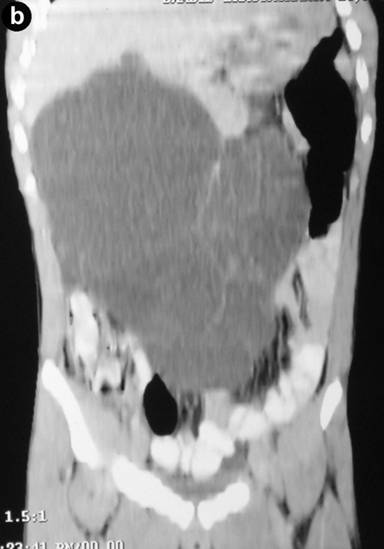

Clinical examination revealed abdominal swelling with generalized tenderness occupying the whole abdomen and almost reaching up to the pelvis. Blood investigation revealed polymorphonuclear leukocytosis (total leukocyte count 12,600 mm-3, reference range: 4,000-11,000 mm-3; polymorphs 91%, reference range: 40-75%). The serum amylase level was 297 U/L (reference range: 20-85 U/L). Liver function tests and CA 19-9 levels were normal. An ultrasound carried out outside our hospital found a large septate cystic collection in front of the pancreas and reported as acute pancreatitis with fluid collection. A CT scan revealed a large multiseptate cystic lesion (23.2x11.7x26.2 cm) anterior to the pancreas reaching up to the pelvis and displacing the gut loops behind and downwards (Figures 1 and 2). We decided to perform a laparotomy with a presumptive diagnosis of cystic neoplasm of the pancreas.

Figure 2. CECT sagittal (a.) and coronal (b.) scan of the abdomen. |